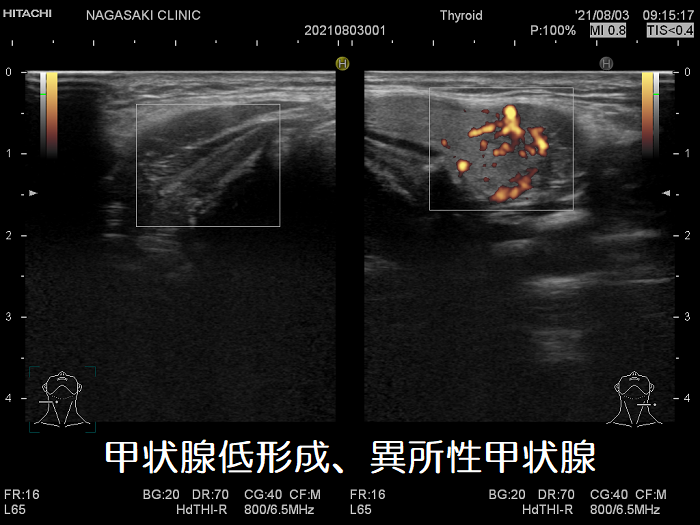

上頚部の異所性甲状腺(甲状腺低形成)

上頚部の異所性甲状腺(甲状腺低形成) 超音波(エコー)画像

上頚部の異所性甲状腺(甲状腺低形成) 超音波(エコー)画像;ほとんど顎下腺の下に異所性甲状腺

上頚部の異所性甲状腺(甲状腺低形成) 超音波(エコー)画像 ドプラーモード

上頚部の異所性甲状腺(甲状腺低形成) 超音波(エコー)画像 ドプラーモード内部血流は正常だが、左側だけしかない